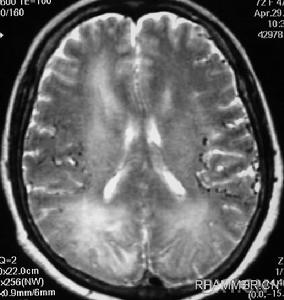

3.影像學檢查一般X線檢查可以確診顱蓋部腫瘤,可見局部骨質增生與外突,亦可有骨質增生與破壞同時存在,有時可見放射狀骨針樣變化,塊影通常呈圓形或橢圓形、邊緣整齊,有時可見不規則外形或蟲蝕樣地圖樣邊緣,尚需拍攝肩胛骨、髖骨、肋骨片,觀察有無類似骨質侵蝕;若為顱底骨瘤,可見突入顱腔內之腫塊,形成密度增高影。若鑑別診斷有困難時,應行DSA、CT、MRI與SPECT等檢查,確定顱內侵入程度。